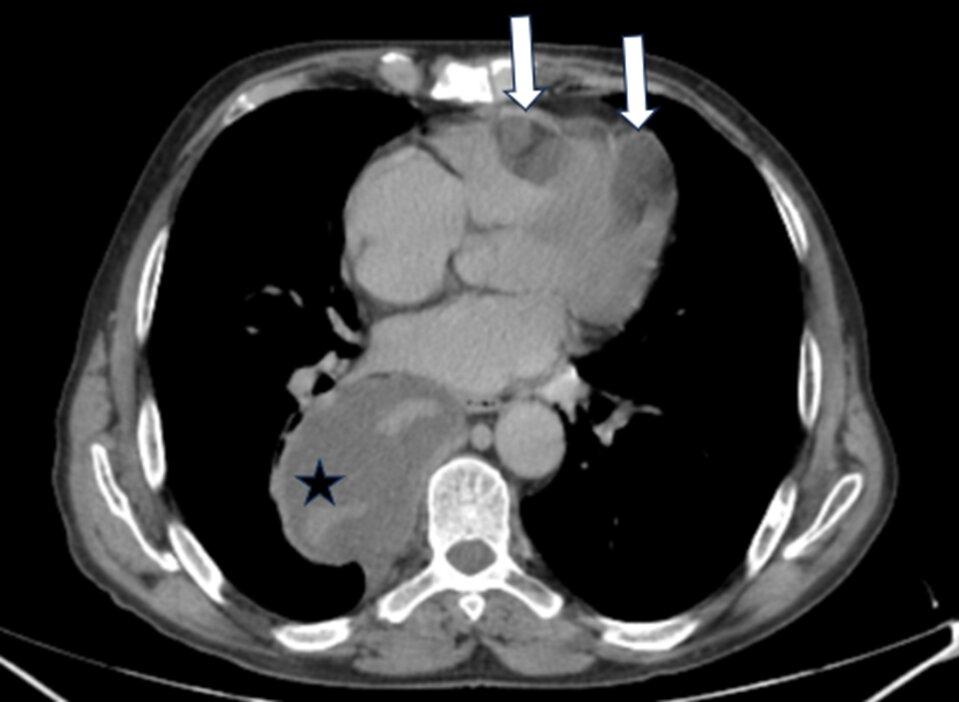

CT扫描示多个非典型位置的转移灶。这些转移灶在影像学上呈现出相似的特征,表现为低密度改变。转移灶的分布广泛,涉及心脏内部(右心室和左心室)、纵隔(后纵隔)、腹腔、左侧前腹壁以及右侧阴囊。

CT 扫描显示两个位于左心室和右心室的低密度病灶,与心包接触(白色箭头),以及位于后纵隔的低密度病灶,与同侧下肺静脉、胸膜和邻近椎体紧密接触(黑色星号)。

CT扫描显示患者的心脏内有两个低密度病灶,分别位于左心室和右心室,且与心包分界不清(白色箭头)。此外,还有一处位于后纵隔的低密度病灶,该病灶与同侧下肺静脉、胸膜以及邻近椎体紧密接触(黑色星号)。